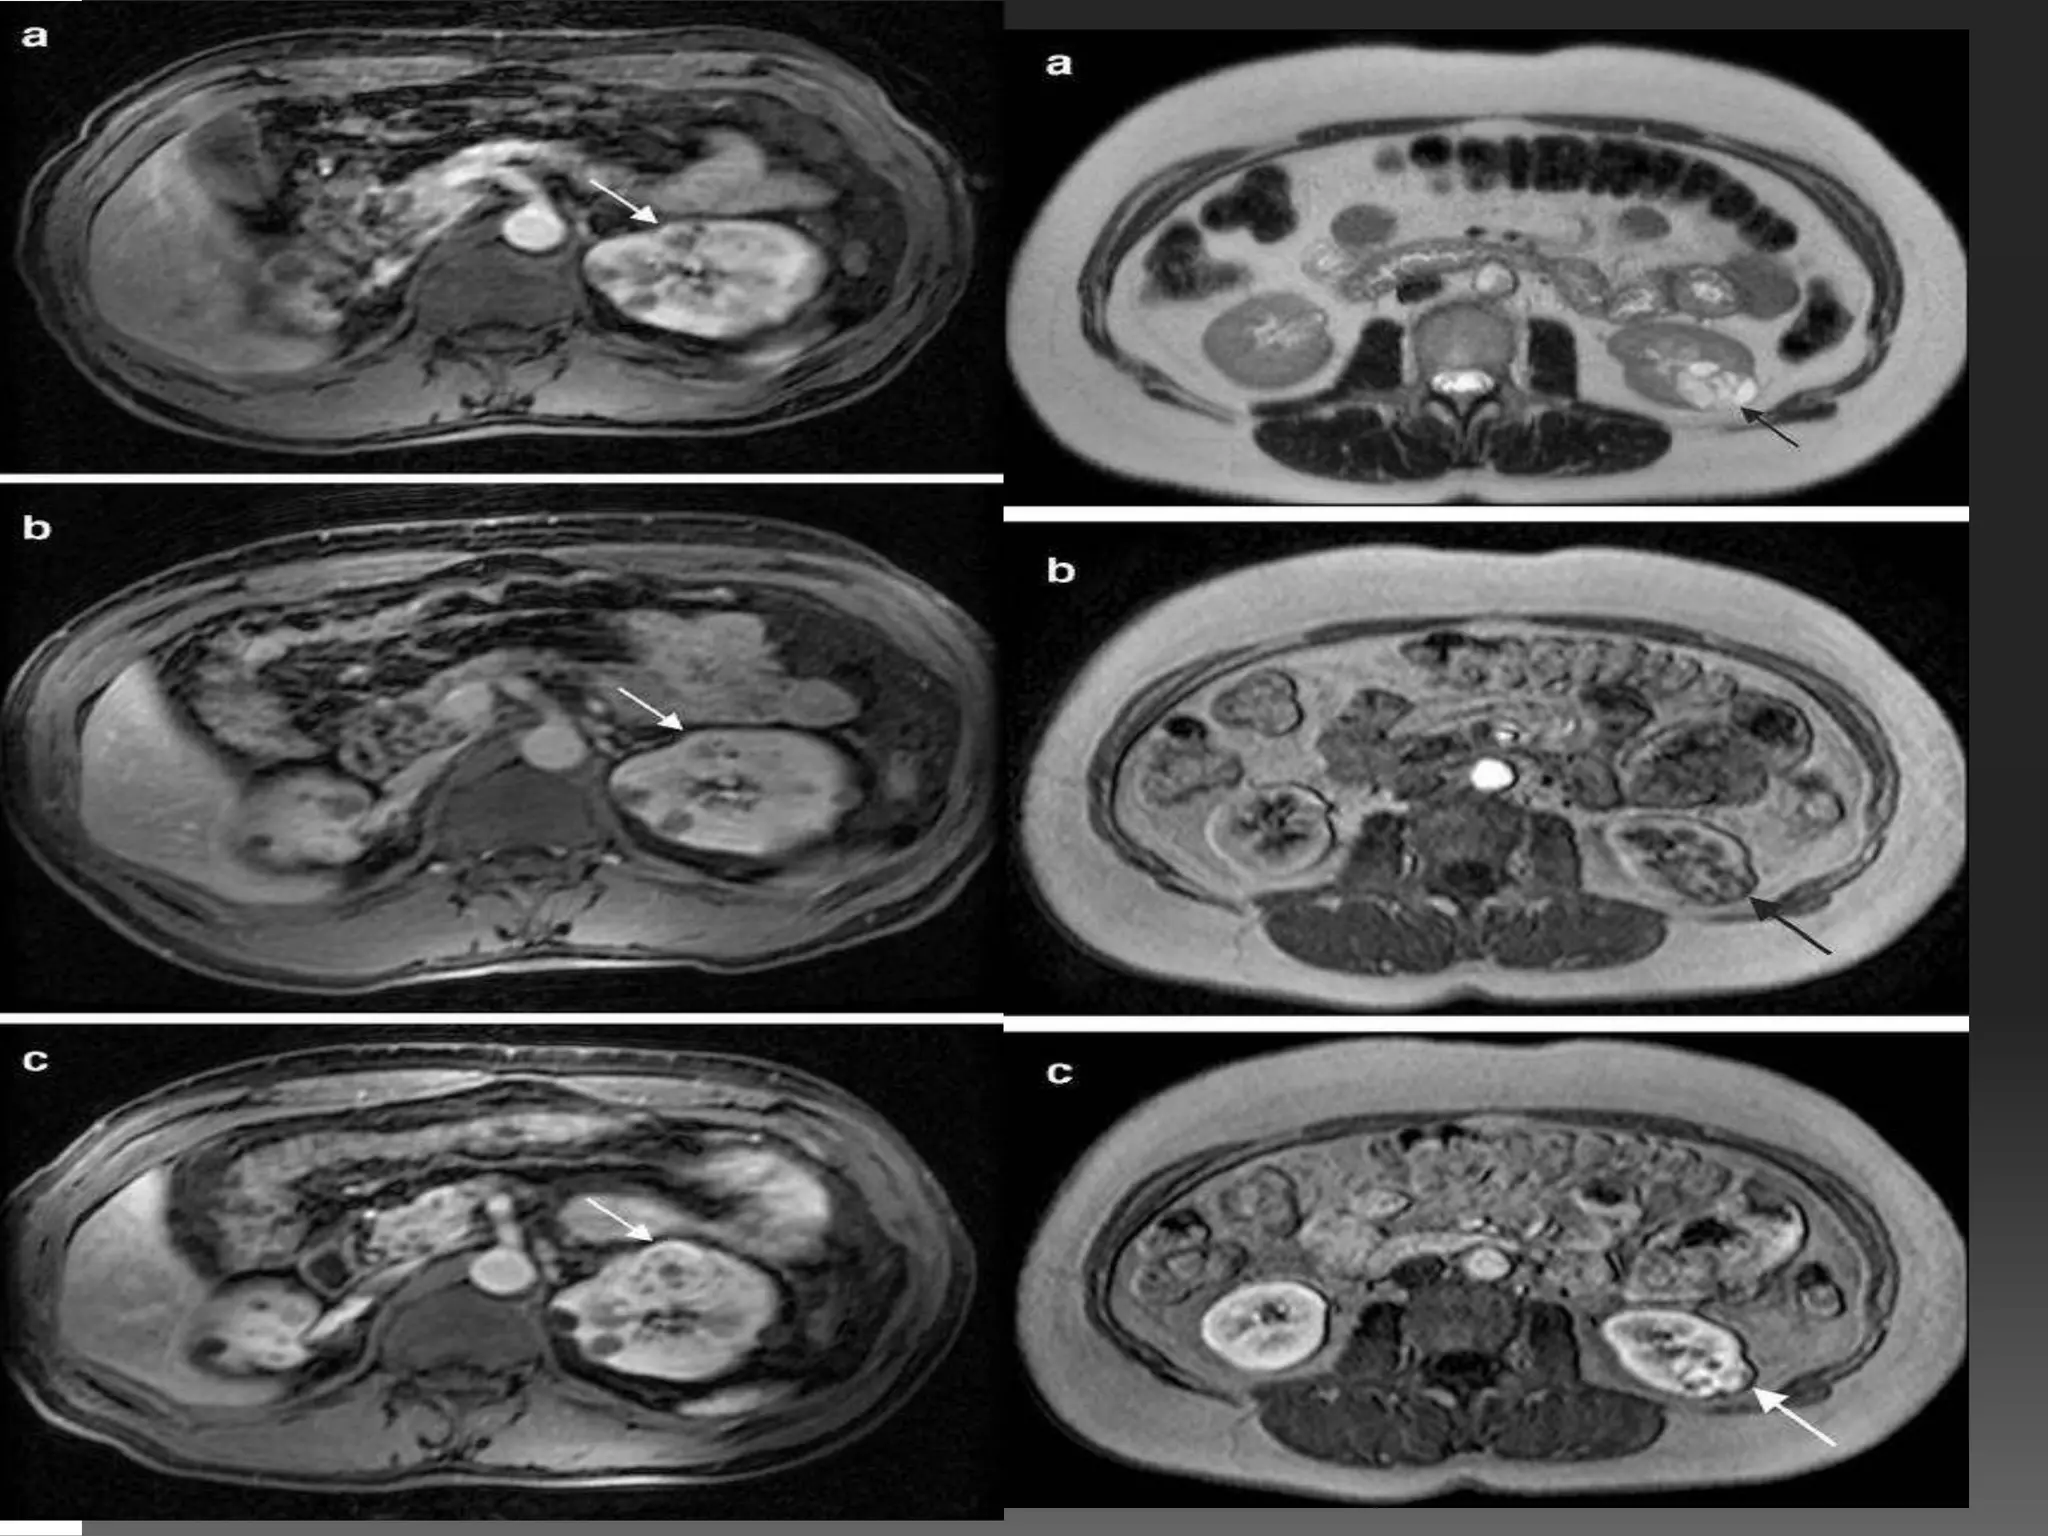

MRI OF GIT SECTIONAL ANATOMY